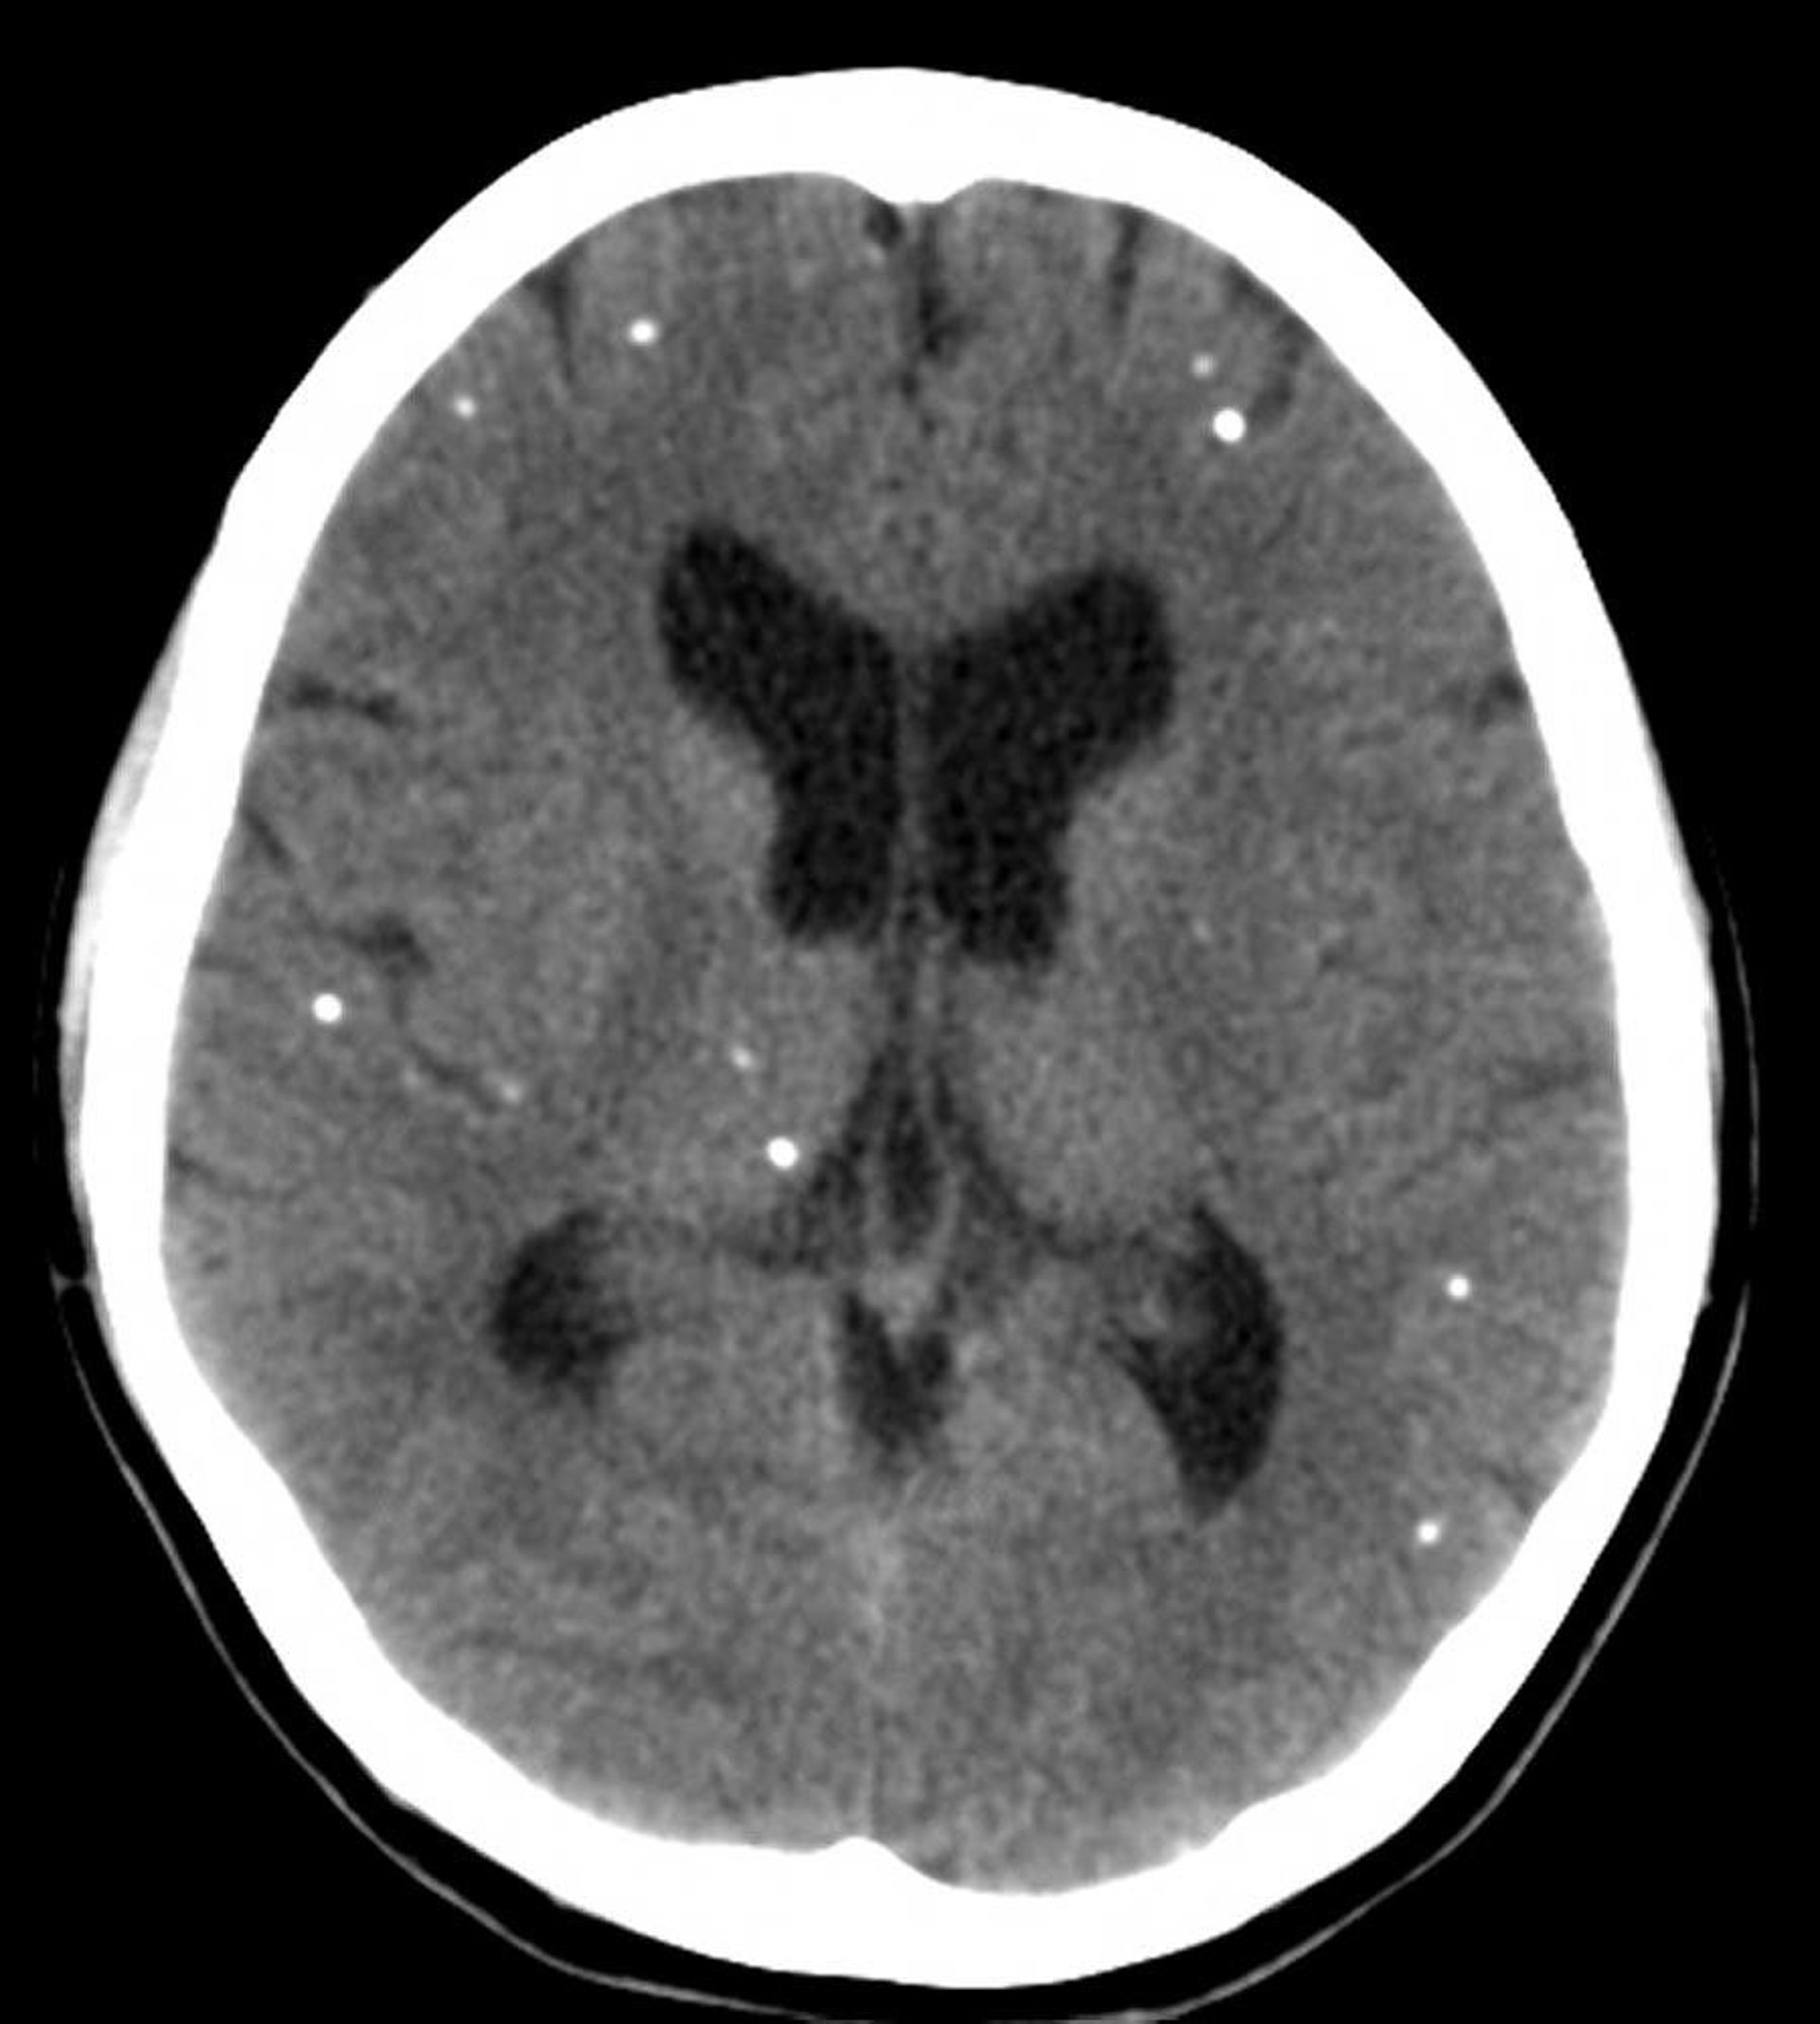

This CT scan shows multifocal areas of calcification representing calcified cysts in a patient with neurocysticercosis.

Courtesy of John E. Greenlee, MD.